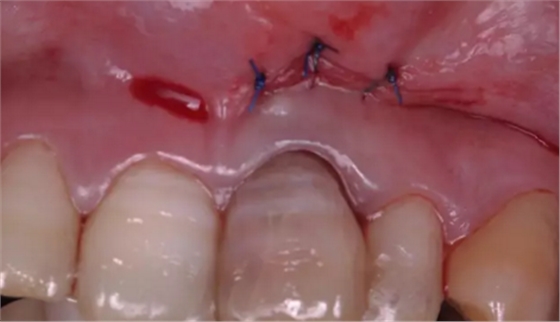

術(shù)后縫合